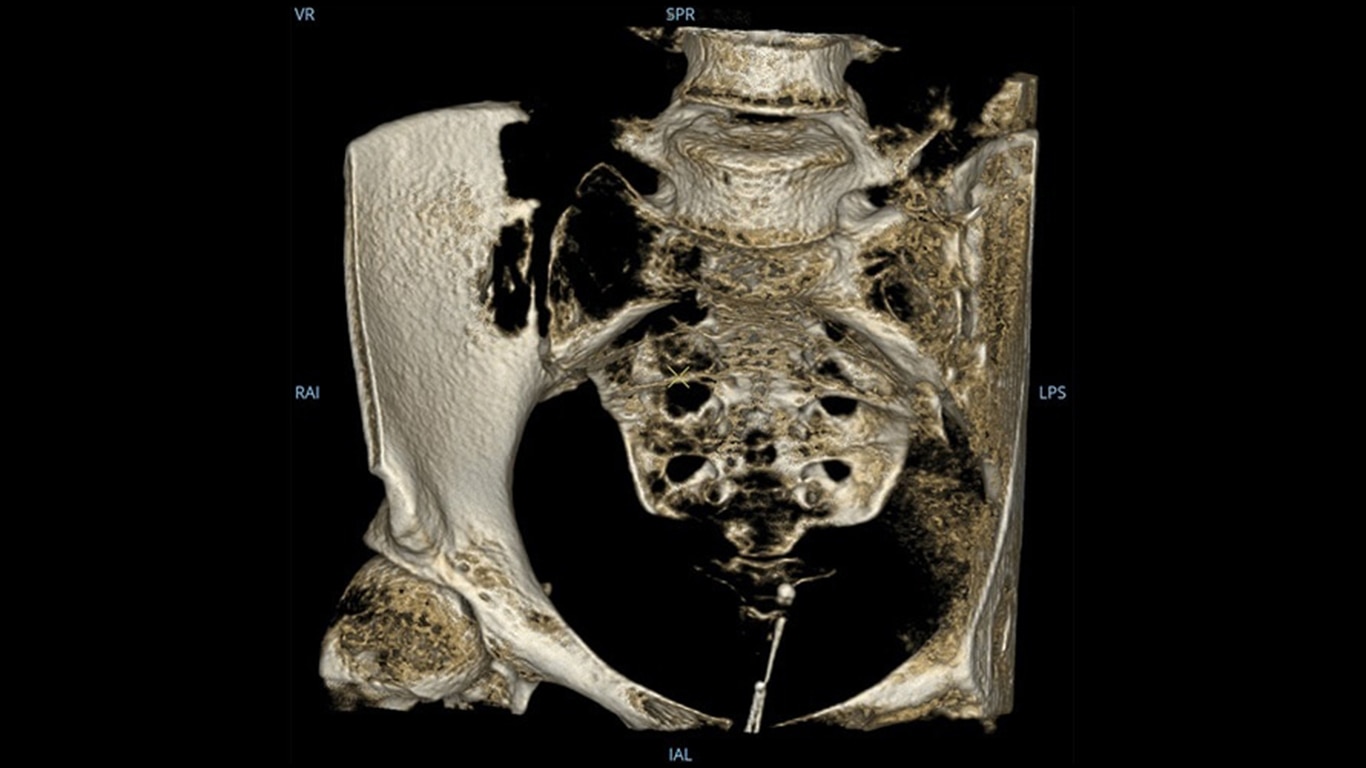

Mehr sehen, schneller entscheiden: Der OEC 3D ermöglicht die gleichzeitige Darstellung mehrerer Ebenen bei verschiedensten Anwendungen. Ob Spondylodesen, komplexe Trauma- Chirurgie oder Bronchoskopien. Mit einem Volumen von 19 × 19 × 19 cm liefert er bis zu 67 % mehr Bildinformationen als vergleichbare Systeme – für mehr Sicherheit und Effizienz im OP.

Analysieren Sie Ihre Scans mit dem GE Volume Viewer – genauso intuitiv wie am CT. Profitieren Sie von der vollständigen Darstellung axialer, koronarer und sagittaler Ebenen sowie von MIP-Ansichten und 3D-Visualisierungen im VR-Modus. Scrollen Sie durch bis zu 512 Schichten mit nahtloser Anpassung der Schichtdicke – für eine präzise Befundung direkt im OP.